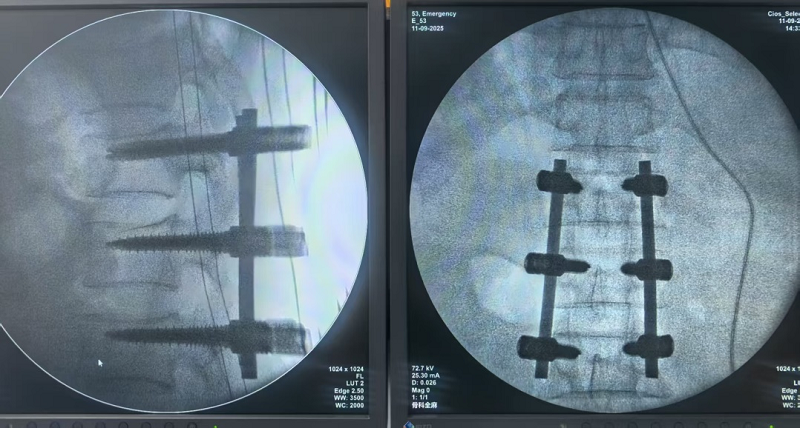

9月11日,同济军山运动医学中心团队完成了自中心成立以来的首例脊柱内固定手术。这标志着中心在脊柱外科领域,为军山新城及周边区域居民提供了更加完善、高水平的医疗健康服务保障。

经过严谨细致的术前评估和准备,9月11日,骨科副主任医师徐勇率领团队为患者实施了“腰椎骨折切开复位内固定术”。

首例脊柱内固定术的成功开展,不仅是中心在脊柱外科领域实现“从无到有”的跨越,更是其综合医疗实力的有力印证。目前,患者术后恢复情况良好,已能在专业指导下进行早期下床活动,康复进程顺利推进。